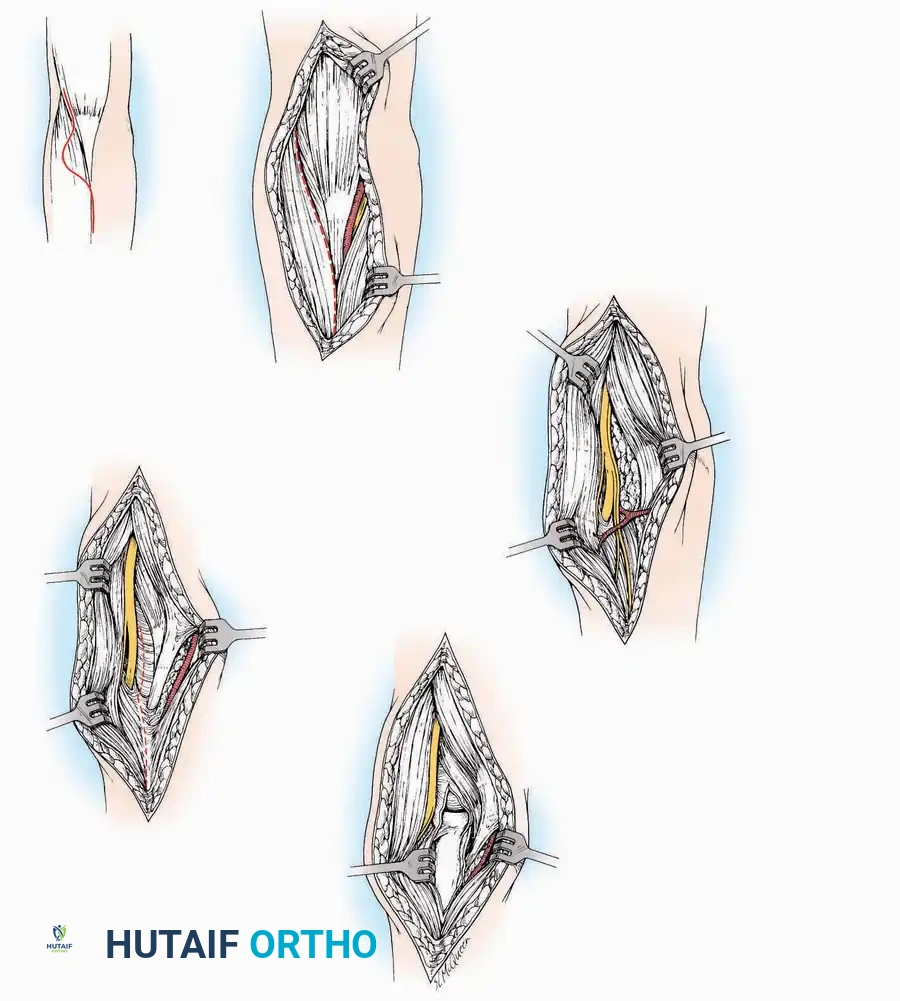

Surgical Technique:

* Incision: Begin the incision on the lateral margin of the Achilles tendon near its insertion. Extend it distally to a point 4 cm inferior and 2.5 cm anterior to the lateral malleolus. (For trauma, a classic L-shaped extensile incision is often used, dropping straight down anterior to the Achilles, then curving gently toward the base of the 5th metatarsal).

* Superficial Dissection: Divide the superficial and deep fasciae. It is imperative to create a "full-thickness" flap containing skin, subcutaneous fat, and periosteum to prevent flap necrosis.

* Nerve Protection: The sural nerve crosses the proximal and distal limbs of this approach. It must be identified and protected within the anterior flap.

* Deep Dissection: Isolate the peroneal tendons (longus and brevis). Incise and elevate the periosteum below the tendons to expose the lateral wall of the calcaneus.

* Tendon Management: If severe deformity or infection is present, the peroneal tendons may be divided via Z-plasty and repaired at the conclusion of the case, though this is rarely necessary in modern fracture care.